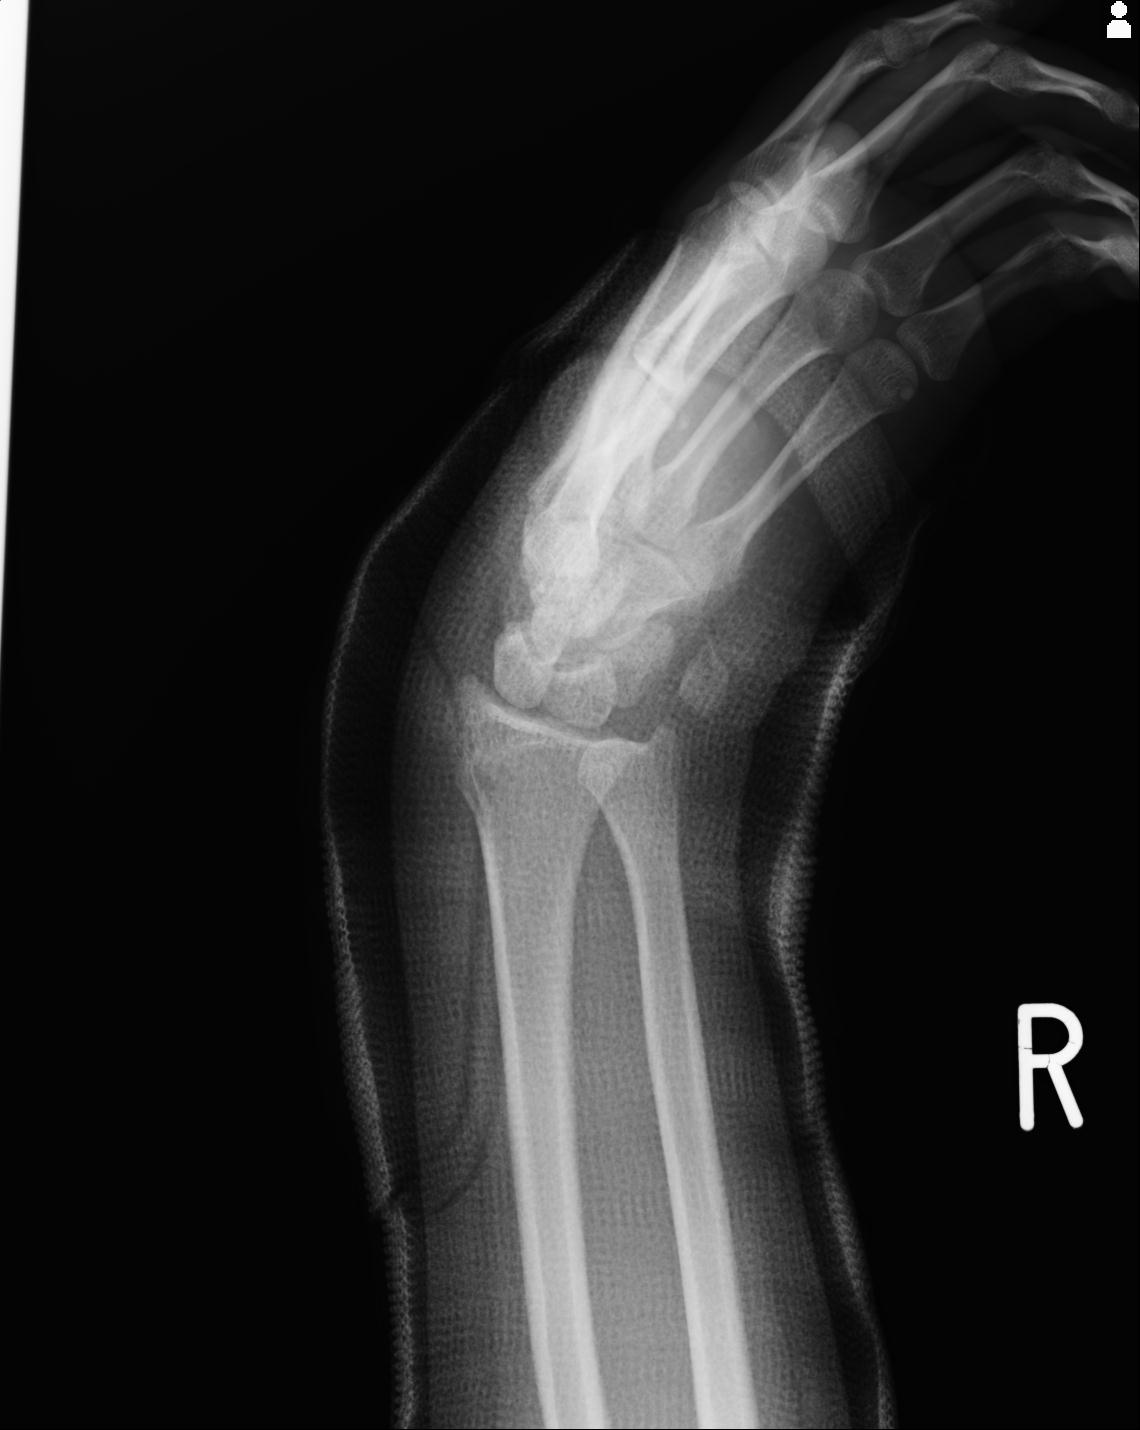

46666 1/23 両股正面+軸と右手関節 2R 76歳女性 右橈骨遠位端

46666 1/28 両股正面+軸と 1/26 右手関節 2R 76歳女性 右転子部骨折